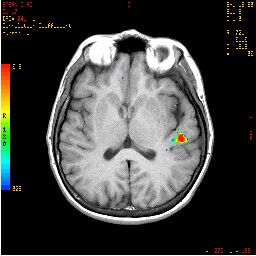

| Activation |

The left hemisphere shows predominant activation. The following areas were activated: Broca's, left posterior portion of middle and inferior temporal gyri (Brodman's 37), left parietal and left premotor strip. Wide activation is seen in the inferior aspect of the occipital lobes. The main activation on the right is located in the inferior aspect of the frontal lobe (Brodman's 11), a finding consistently seen in this paradigm. |